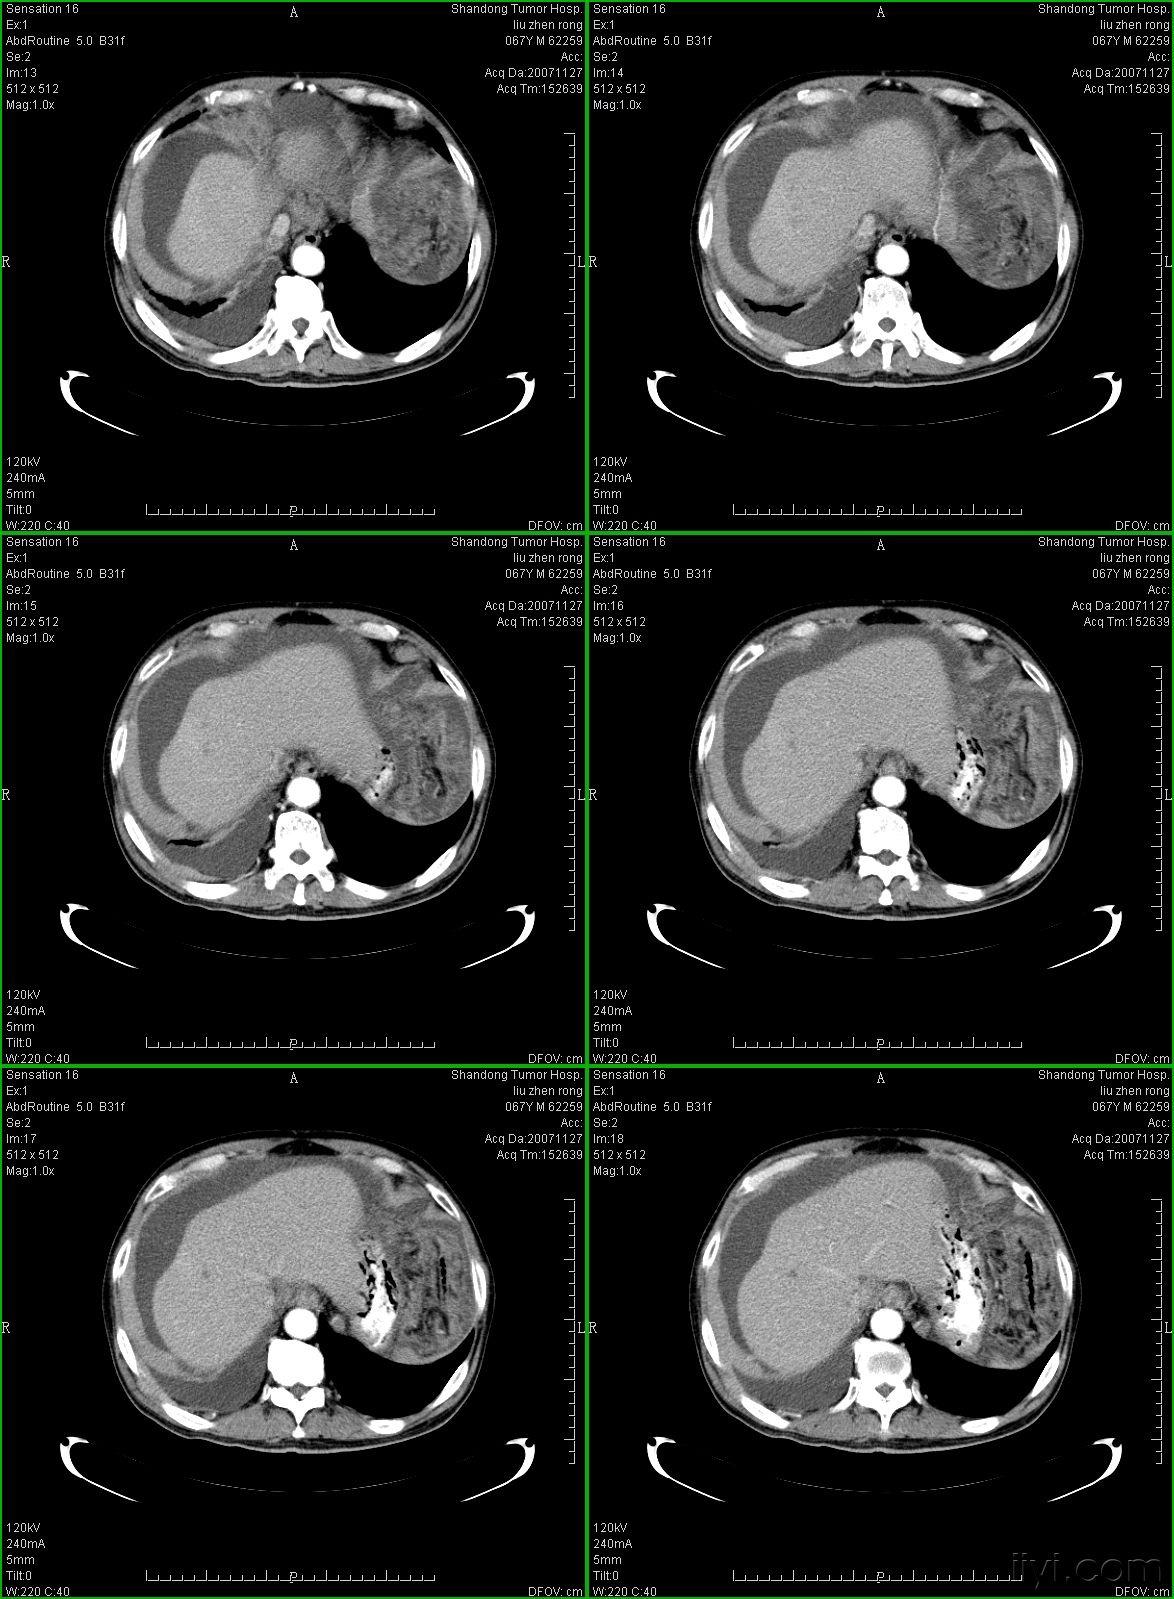

典型的大网膜,肠系膜转移瘤,很经典

图2a大网膜成饼状(ct腹腔横断图象上出现肠曲被前面及两侧的肿瘤组织